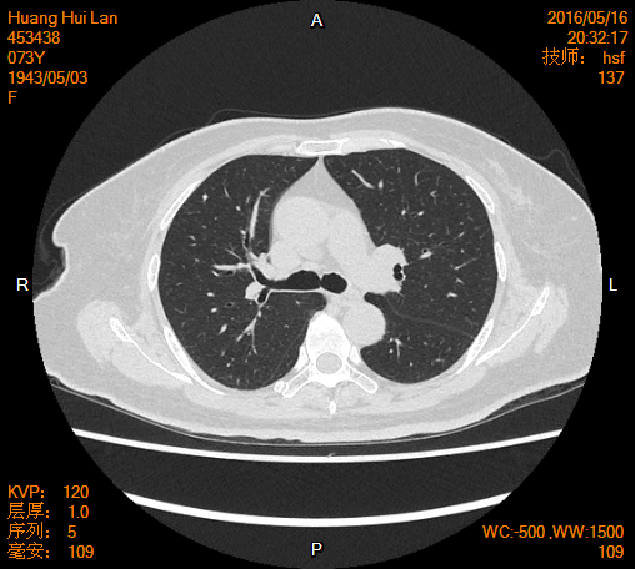

2016-04-13胸腹盆CT

2016-05-17胸腹盆CT(术后基线)